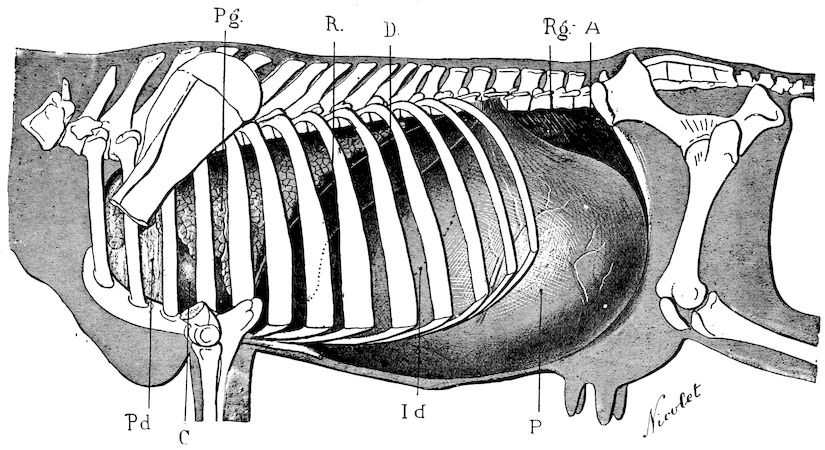

Lesions. The chief lesions are to be found in the bones. They consist in rarefaction of the compact tissue, increase in size of the medullary cavity and Haversian canals, and enlargement of the areolæ of the spongy tissue. The bone marrow loses its fatty constituents, appears red and gelatinous, and contains a greatly exaggerated number of blood-vessels. When heated, the bones do not yield oil as in healthy subjects, and when dry, they seem abnormally porous. In the osteoclastic phase, the bones become very friable and even the shafts assume 17a spongy appearance. They diminish in density. These changes correspond to the stages of eccentric rarefying ostitis and osteoporosis of German authors.

The flat bones often show well-marked periostitis, but the great thickening sometimes seen in certain of the bones of the head appears to be the result of a special osteo-periostitis. It is quite certain that the disease is due to something more than a mere want of mineral constituents in the bone, and poverty in this respect certainly does not explain the hypertrophic changes. The nutrition of the bones as a whole is disturbed, resulting in alterations both in the ossein and in the mineral salts, the whole process being accompanied by symptoms of osteo-periostitis.

Fig. 8.—Transverse section through the middle region of the face in a pig suffering from osseous cachexia.

The fractures which occur so frequently during the osteoclastic phase have well-marked peculiarities. The extravasation of blood is trifling, and no callus forms, even when the ends of the bones are immobilised by external aid; if the ends are left free, they soon become worn and polished by rubbing against one another.

In the neighbourhood of the articulations and ligamentous insertions the periosteum soon undergoes change, and it is not uncommon to find sub-periosteal and intra-osseous extravasations of blood.

18In the final stages, the bones may be cut with a knife, and a time arrives when bony tissue seems completely to have disappeared; thus, as shown in Fig. 8 herewith, it was possible to cut the entire head of a pig into thin slices without the slightest difficulty. All parts of the head had been affected by the softening change.

From the chemical point of view, the diminution in mineral salts and in phosphate of calcium has long been recognised, but the degree of this change varies according to the phase. In human beings the proportions have been estimated as follows: Normal bone, 50 to 80 per cent. of phosphate of calcium; bone in persons suffering from osteomalacia, 5 to 20 per cent. of phosphate of calcium. The changes in the ossein have not been carefully studied. We only know that histologically the ossein becomes fibrillar, and that chemically it no longer retains its normal composition.